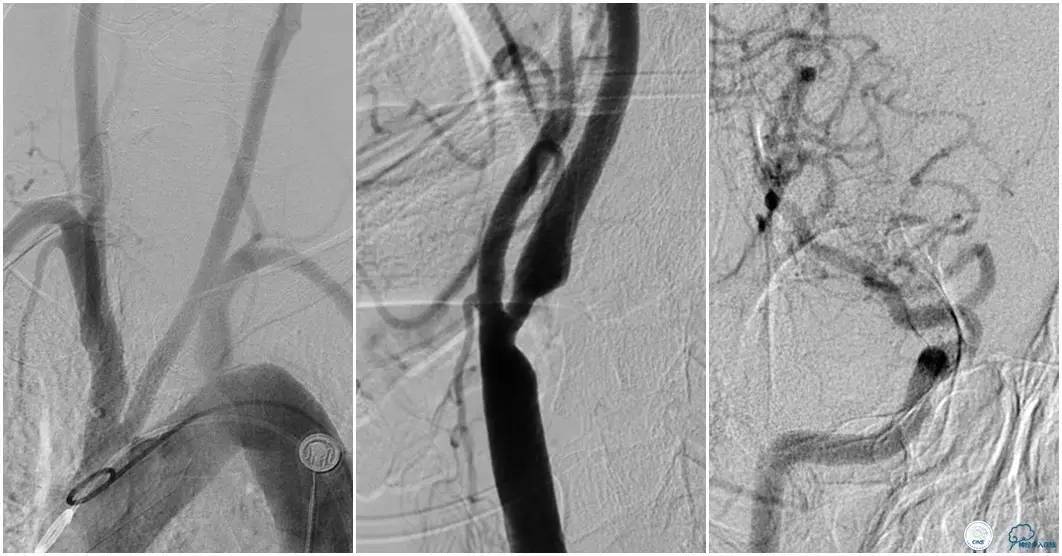

12:35穿刺成功,TOT 185min。3型主动脉弓,右侧颈内动脉起始部狭窄70%,右侧大脑前动脉A1段未显影。

双侧大脑前动脉A4段闭塞,右侧大脑前动脉由左侧大脑前动脉经前交通动脉代偿供血。